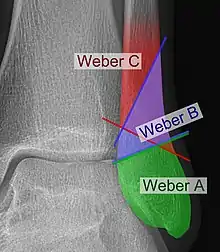

The Danis–Weber classification (often known just as the Weber classification) is a method of describing ankle fractures. It has three categories:[1]

- Type A

- Type B

- Type C